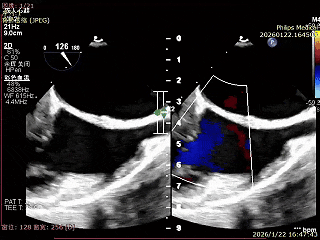

术前超声影像

左室长轴超声可见大量反流

可见二尖瓣明显反流

术后超声影像

左室长轴超声无明显反流

二尖瓣反流可见改善